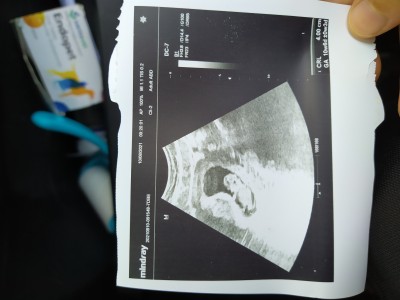

merhaba ben 22 Mayıs'ta adet olmuştum doktor iki hafta evvel adet tarihin yanlış bu bebek 8 haftalık demişti şimdi gittim adetime göre baktı galiba 11 haftalık haftaya  taramaya git dedi ama bana bebek küçük gibi geldi ense kısmı pütürlu gibi geldi anlayamadım 4 cm diyor kaç haftalıkken 4 cm olur? Bebeğim kaç haftalık anlayamadım gitti ikili taramaya gitmem lazım ikili tarama ne zaman yapılır?

Gebelik haftası 11